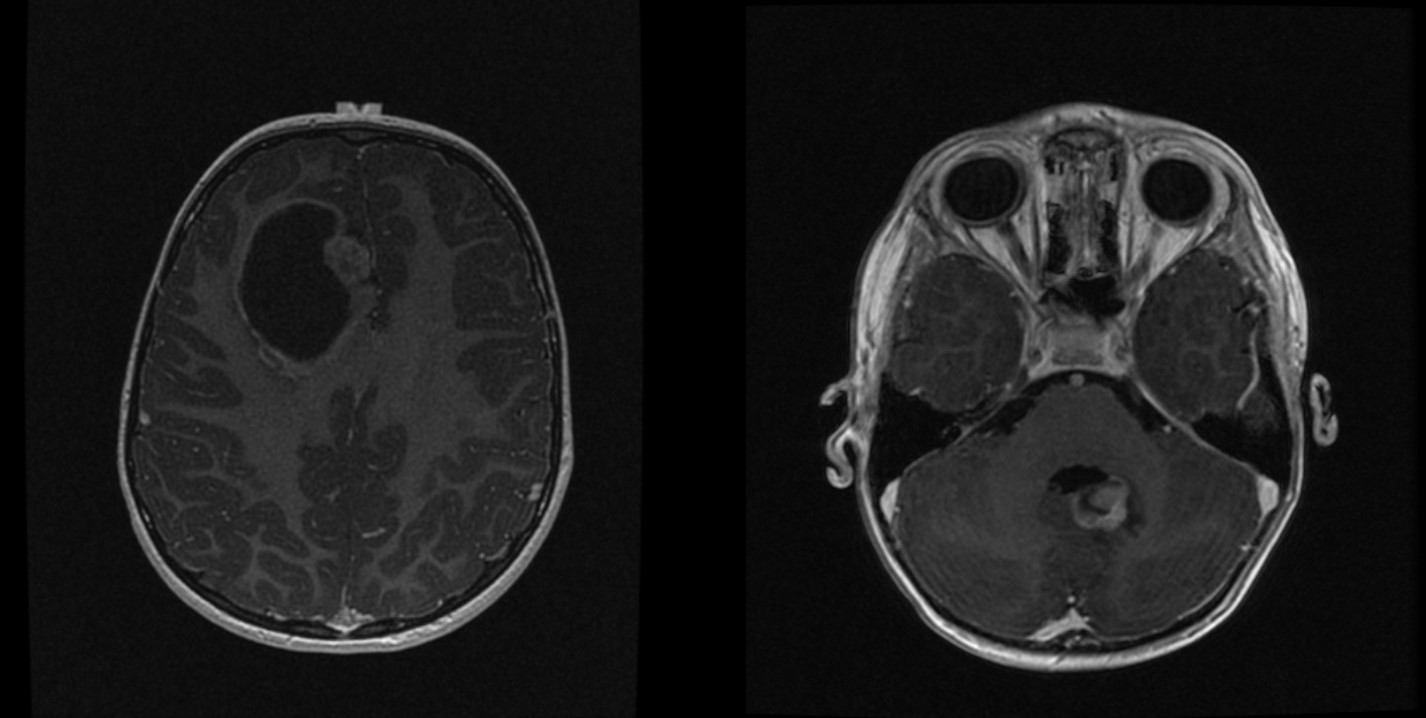

MR_original_(left)_and_cerebel…